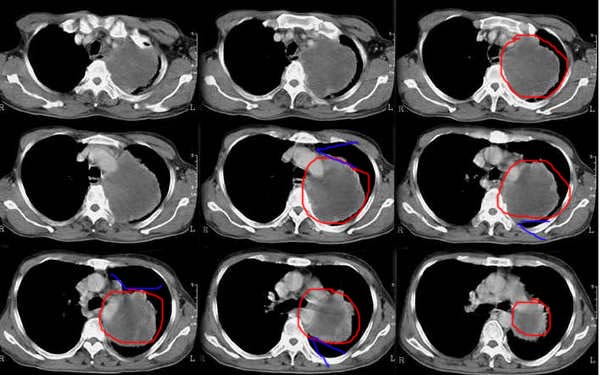

以下是引用乡医在2006-5-15 11:05:00的发言:[br]定位:来自纵隔[br]影象:与纵隔关系密切,类圆形,有膨胀感,有完整的壁及壁结节强化,内部密度均匀。[br]临床:男,60,胸不适半年,近有发热,无咳嗽咳血,平素体健无体检史。[br]影象意见:支气管囊肿合并感染。建议病理确诊。

以下是引用逸风在2006-5-15 17:08:00的发言:[br]ct所见各位老师描述很全面,不再赘述.补充一点,右侧镉肌局限性升高.[br]定位:左后上纵隔.从平片看,肿块外缘肺纹理呈弧形受压改变.横断扫描肿块在肺门周围靠后,肺门及气管位置未见明显移位.外周肺野未见明显阻塞性改变.[br]定性:恶性可能大.肿块边缘不光整,可见强化壁结节,内部有轻度不均匀强化密度,部分层面肿块与主动脉分界不清.右肺中叶小结节影.[br]诊断意见:左侧后上纵隔囊实性占位,考虑来源于神经源性肿瘤,恶性可能大.[br]建议:1.穿刺活检,明确诊断.2.b超右膈下检查,排外膈下病变.